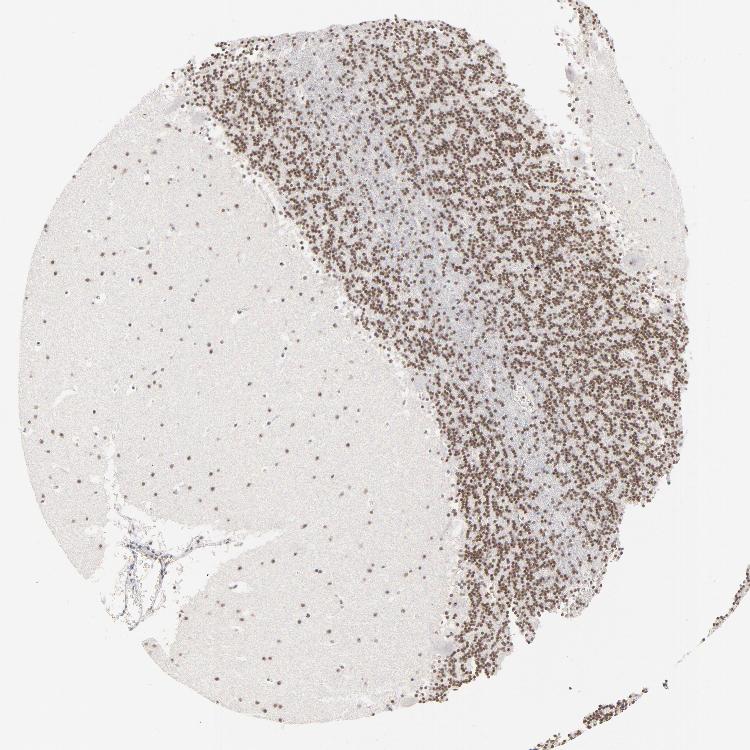

CEREBELLUM - Antibody stainingi

Antibody staining in the annotated cell types in the current human tissue is reported as not detected, low, medium, or high, based on conventional immunohistochemistry profiling in selected tissues. This score is based on the combination of the staining intensity and fraction of stained cells.

Each image is clickable and will lead to virtual microscopy that enables deeper exploration of all samples and also displays staining intensity scores, fraction scores and subcellular localization as well as patient and tissue information for each sample.

Antibody HPA003263

Purkinje cells Medium

Cells in granular layer Medium

Cells in molecular layer Low